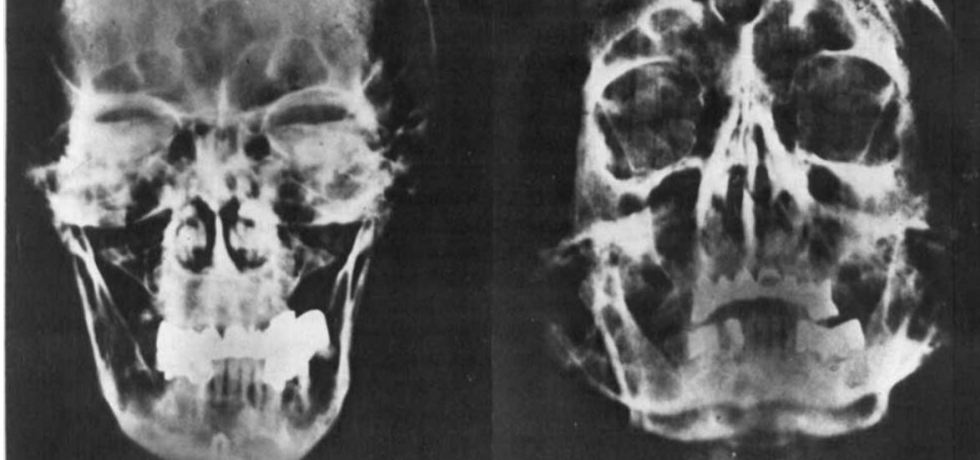

Uusi tutkimus Hitlerin hampaista katkaisee siivet salaliittoteorioilta

Tekijä Kalmistopiiri20.5.201811.4.2020